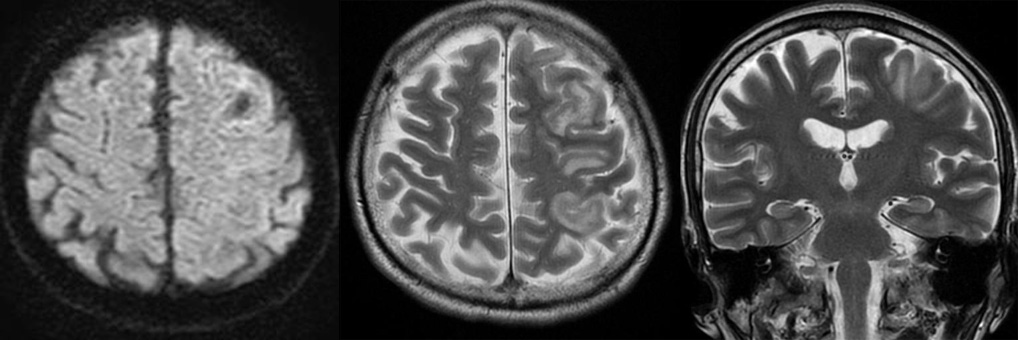

52才 男性

主訴:痙攣

現病歴:昨日より右手が動かしにくかった。朝7時頃起床。朝ご飯を食べようとして台所で痙攣を起こして倒れた。初めての症状。1回嘔吐したら意識情明になった。

症例3

8才 男児

主訴:発達障害